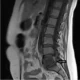

La artritis tuberculosa es una infección de las articulaciones periféricas causada por Mycobacterium tuberculosis, que generalmente se presenta como una artritis monoarticular de curso prolongado, que puede durar desde semanas hasta meses o incluso más tiempo. Aunque menos frecuente, en algunos casos puede presentarse de manera aguda, mimetizando una artritis séptica. Esta condición puede afectar cualquier articulación del cuerpo, pero las más comúnmente involucradas son la cadera y la rodilla. A diferencia de otras infecciones articulares, los síntomas constitucionales y la fiebre no suelen ser prominentes en la artritis tuberculosa.

Además de la artritis en sí, la tuberculosis puede causar una tenosinovitis crónica en la mano y la muñeca, así como dactilitis, una inflamación difusa de los dedos. La destrucción articular en la artritis tuberculosa progresa de manera más lenta en comparación con la artritis séptica, que es causada por organismos piogénicos, debido a las características propias de la infección por Mycobacterium tuberculosis. La fluidez sinovial en la artritis tuberculosa es típicamente inflamatoria, pero no alcanza los niveles de inflamación observados en las infecciones piogénicas. En términos de recuento de células blancas en el líquido sinovial, este se encuentra generalmente en el rango de 10,000 a 20,000 células por microlitro (10-20 × 10⁹/L).

En cuanto al diagnóstico, los frotis del líquido sinovial pueden ser positivos para bacilos ácido-alcohol resistentes en una minoría de los casos, lo que ayuda a confirmar la presencia de Mycobacterium tuberculosis. Sin embargo, las cultivos del líquido sinovial son positivos en aproximadamente el 80% de los casos. Dado que los resultados de los cultivos pueden tardar varias semanas, el procedimiento diagnóstico más efectivo y utilizado con mayor frecuencia es la biopsia sinovial, que suele proporcionar hallazgos patológicos característicos y cultivos positivos en más del 90% de los casos.